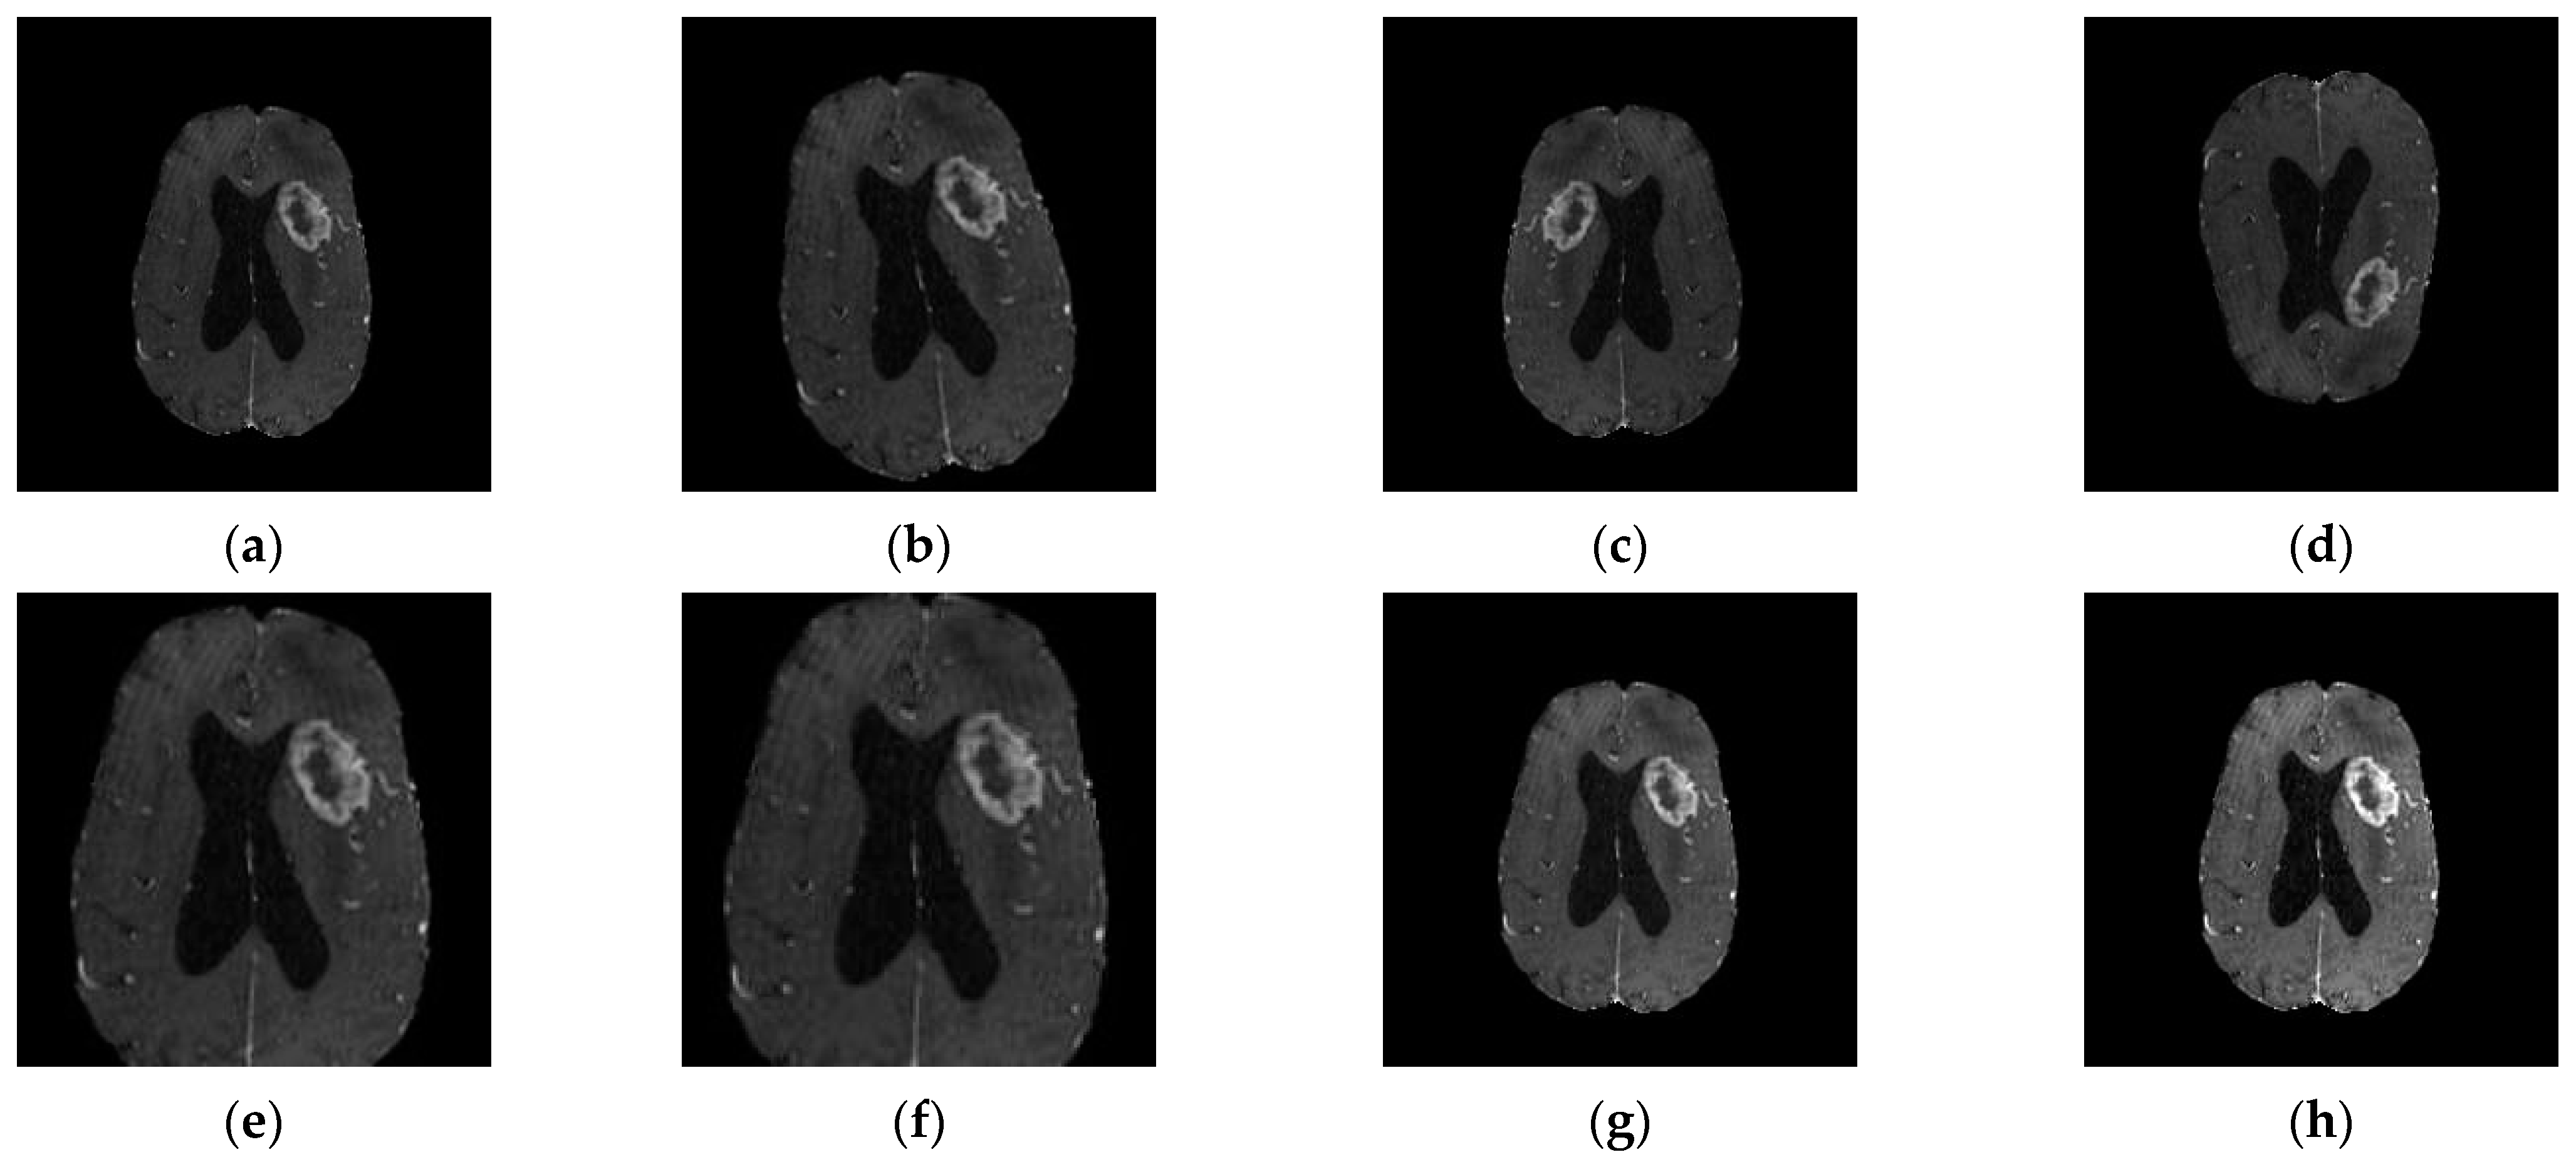

| Sequence | Sequence Characteristics | Main Clinical Distinctions | Example * |

|---|---|---|---|

| T1w | Uses short TR and TE [64] |  | |

| T2w | Uses long TR and TE [64] |  | |

| ceT1w | Uses the same TR and TE as T1w; employs contrast agents [64] |

|  |

| FLAIR | Uses very long TR and TE; the inversion time nulls the signal from fluid [67] |  |